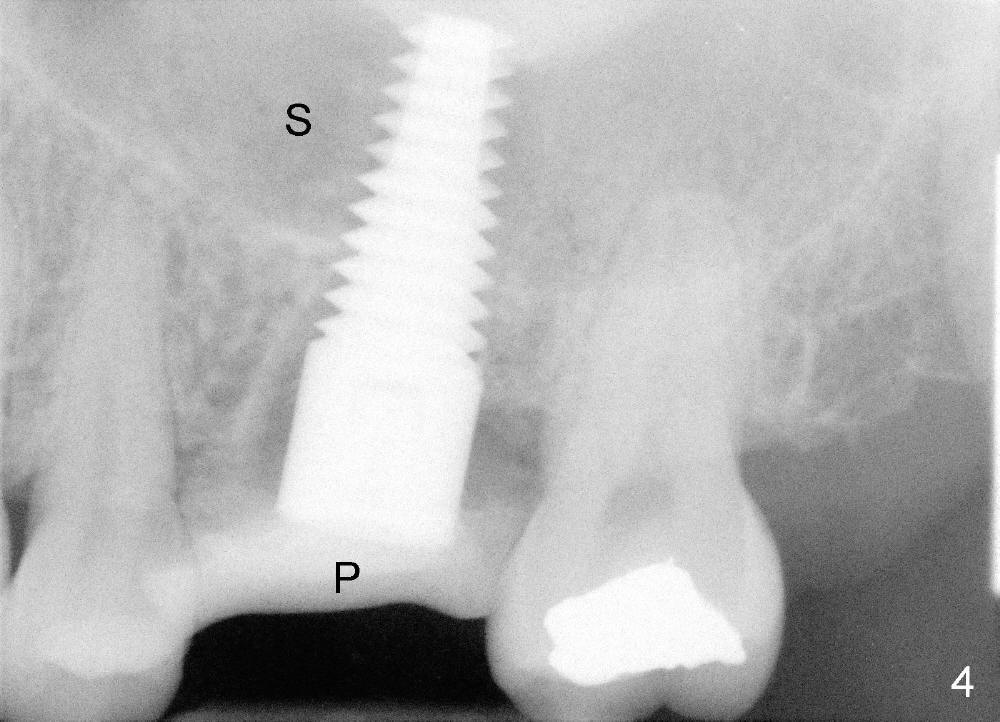

A 49-year-old lady has toothache at the upper left 1st molar (Fig.1).  Removal of the occlusal amalgam reveals crack lines (Fig.2).  After atraumatic extraction (sectioning), osteotomes are used to form osteotomy in the septum (Fig.3 S).  Finally the osteotomy seems to drop into the palatal socket.  No bone graft is used.  The socket is closed by elavating the buccal flap (Fig.3) and severing the periosteum.  Periodontal dressing is applied for wound protection (Fig.4 P). Is the implant in the sinus (S)?